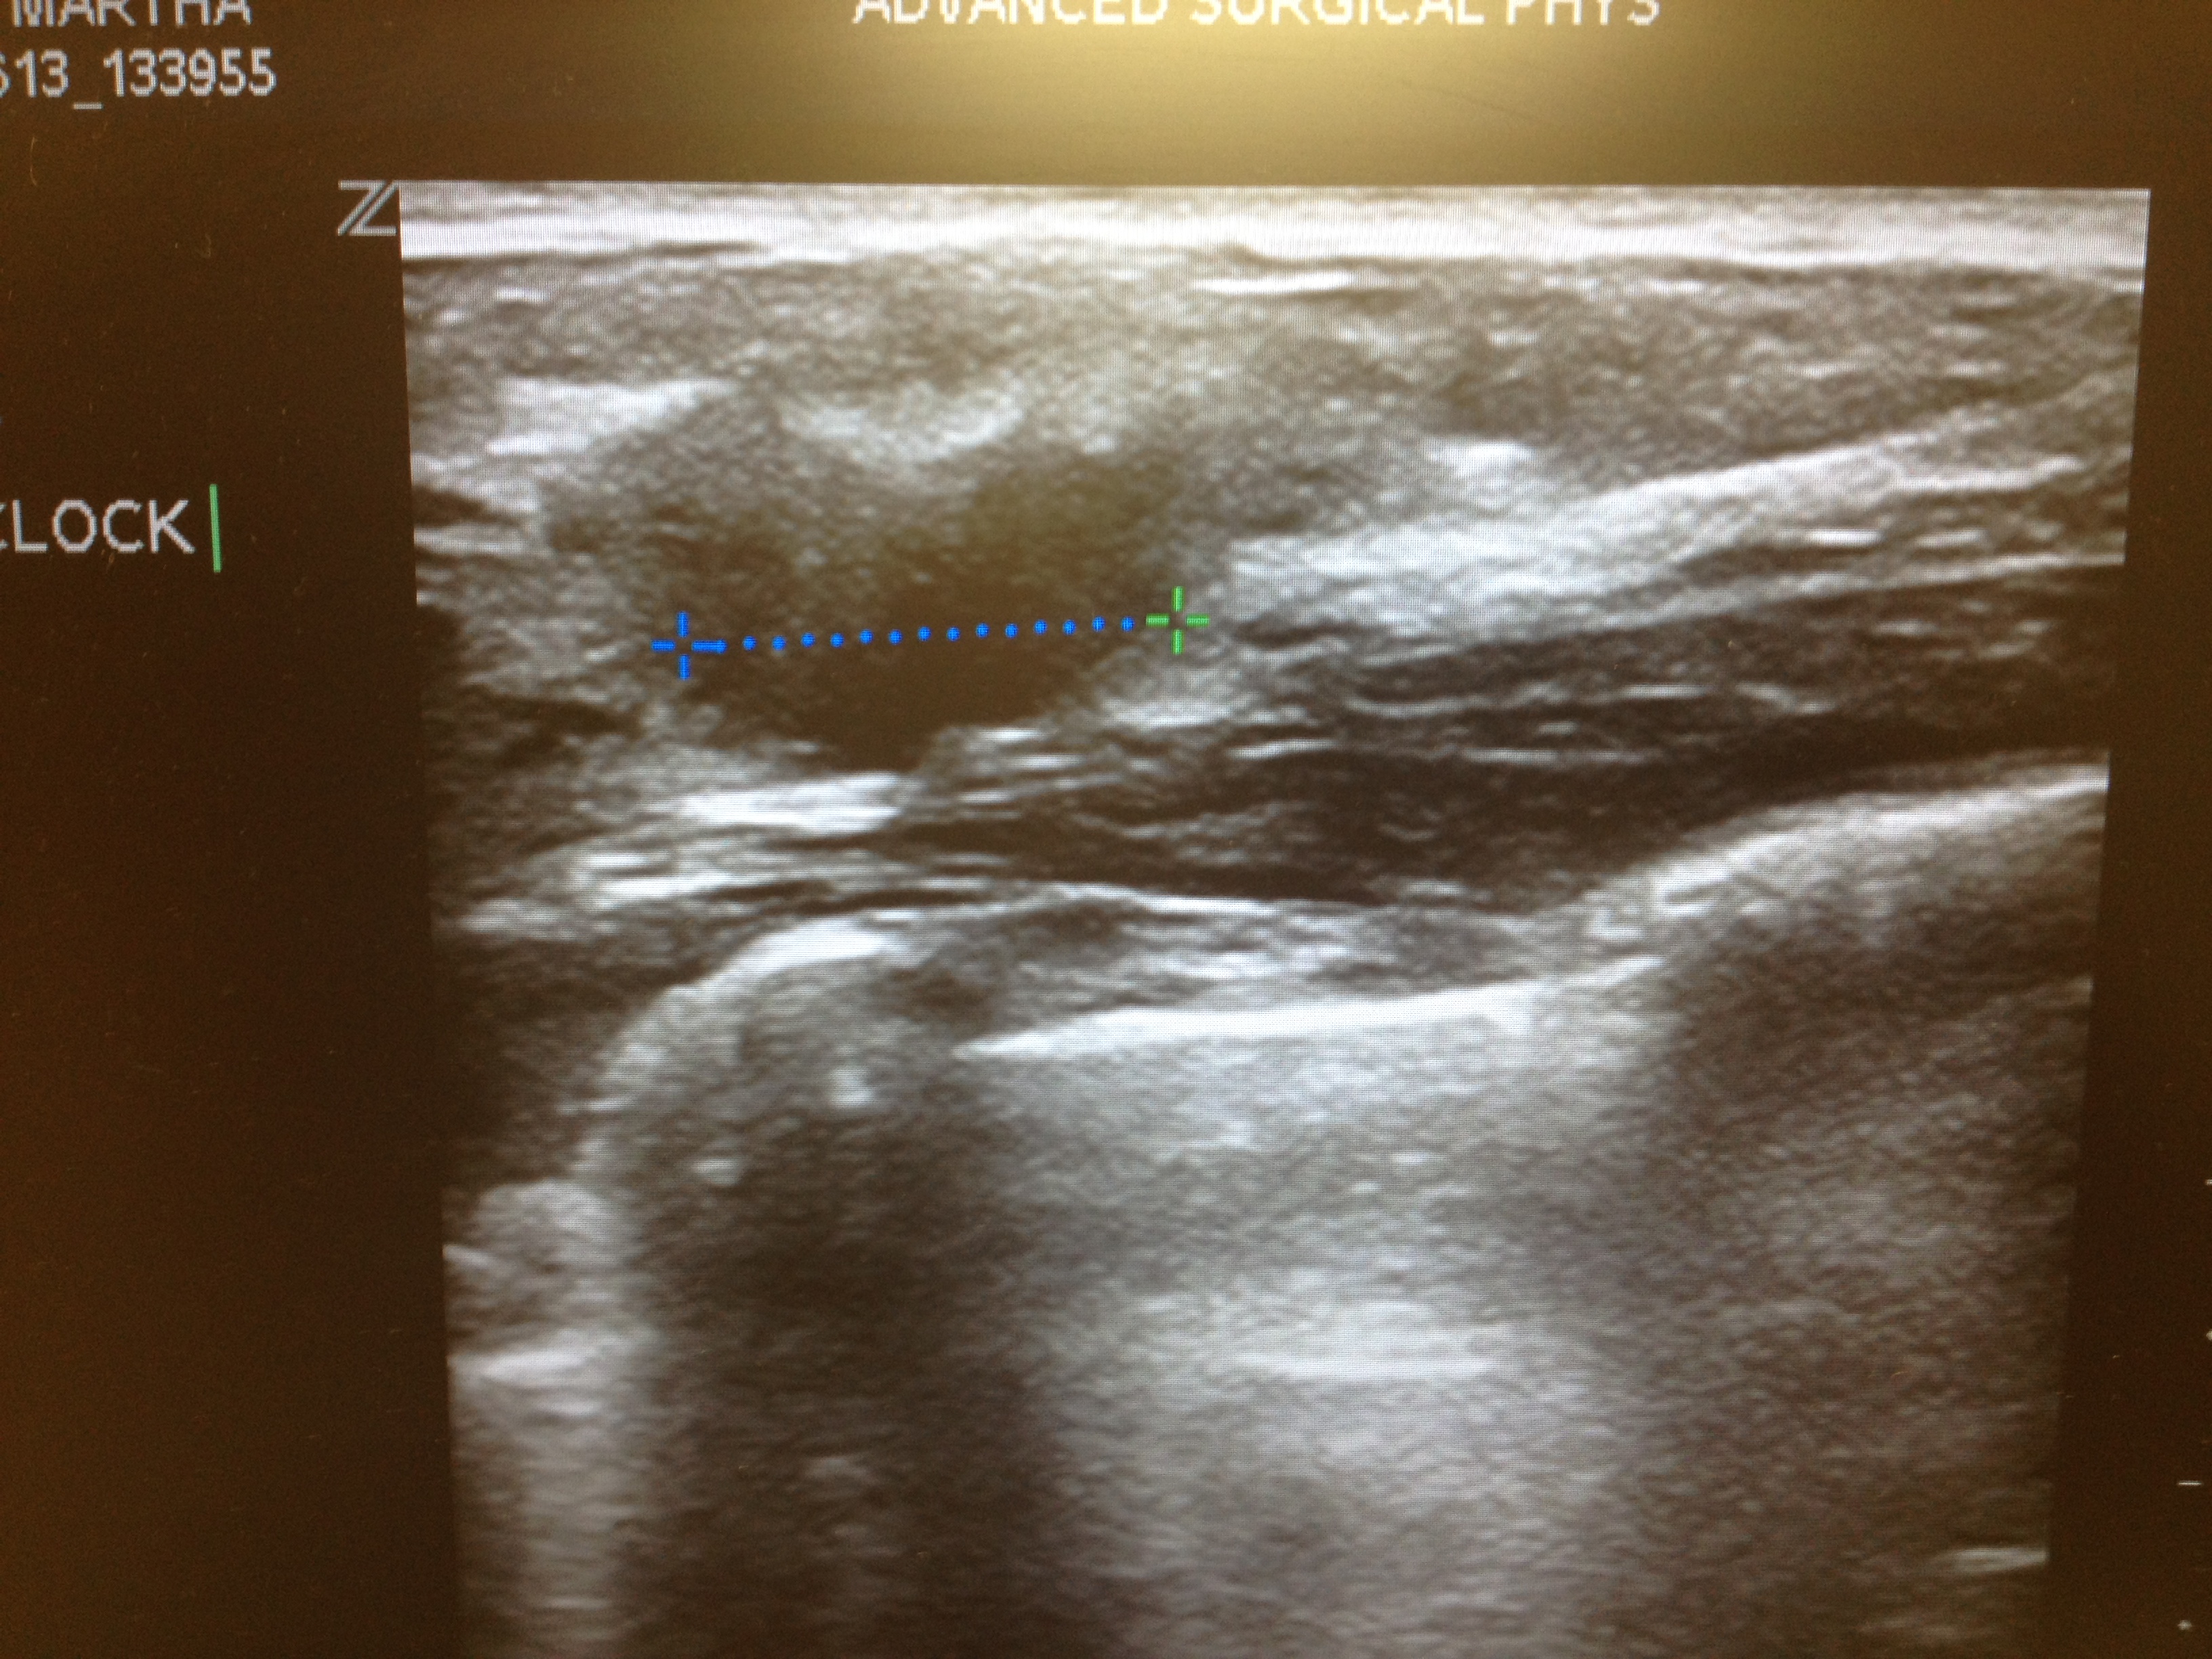

I took a picture of the tumor on the ultrasound screen before I left. I'm not sure why, but I did. Here it is — all 1.8 cm of it.